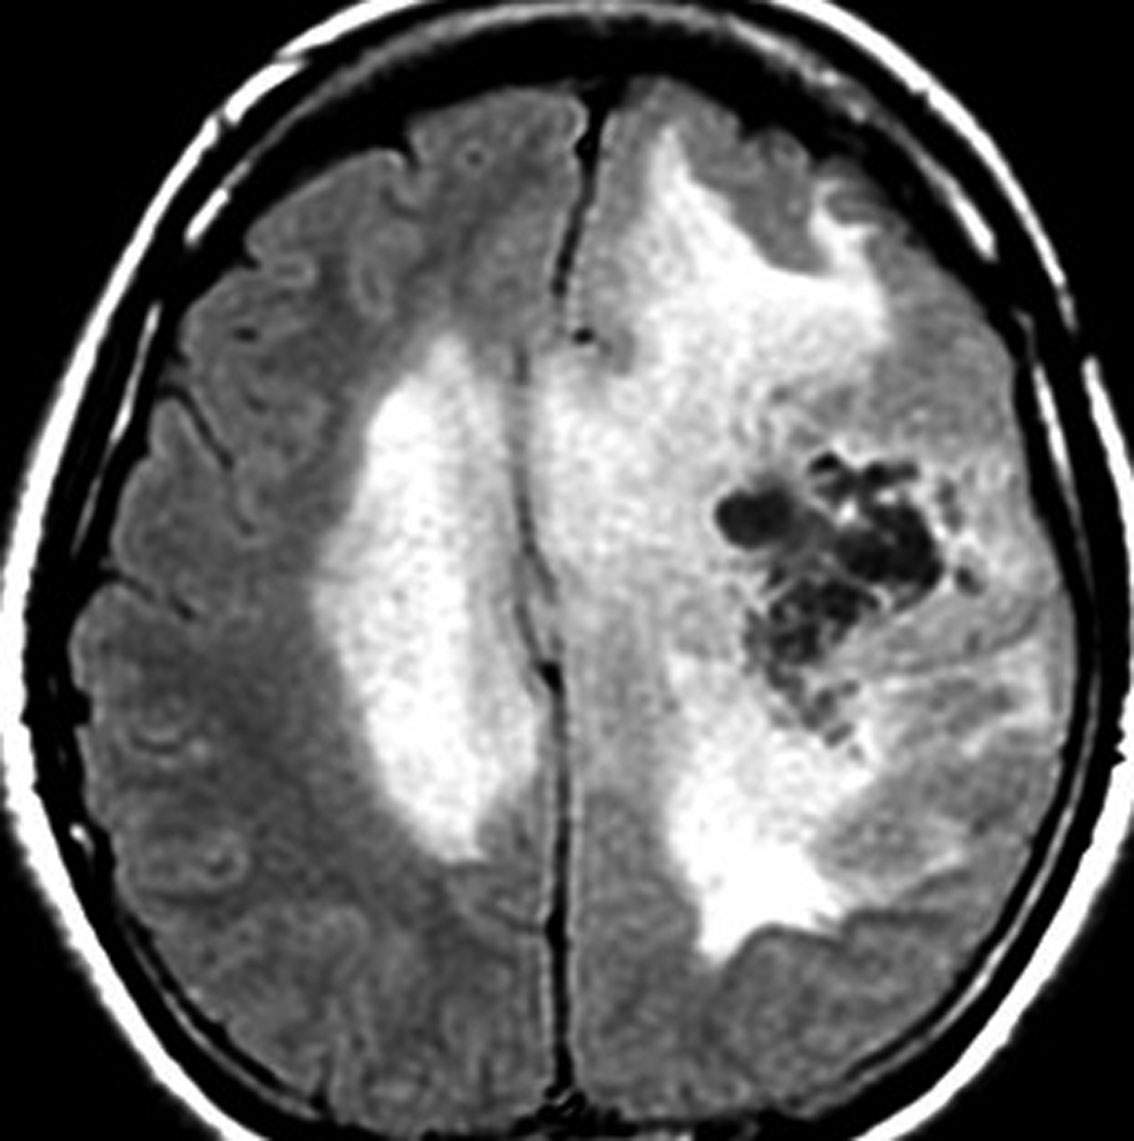

グリオマトーシスのような星細胞腫があります

軽度の左下肢の麻痺で発症した50代の患者さんです。一見,かつてのグリオマトーシス gliomatosis あるいは diffuse hemispheric glioma WHO grade 4 のように見える非常に広範囲な病変です。しかし,病理診断は 星細胞腫 IDH mutant WHO grade 2でした。

放射線治療によく反応し,片麻痺は消失して,画像上の腫瘍高信号もほぼ消失しています。